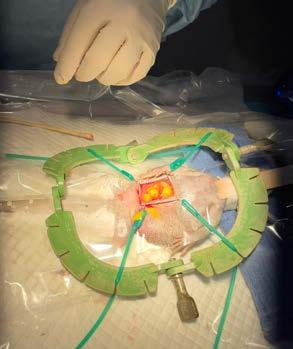

A Canine Desexing Model Utilised by 3rd Year Students in a Tutorial Prior to Their First Live Animal Spey .................................................... 38 Transform Your Passion into Impact: Join Our PhD Program